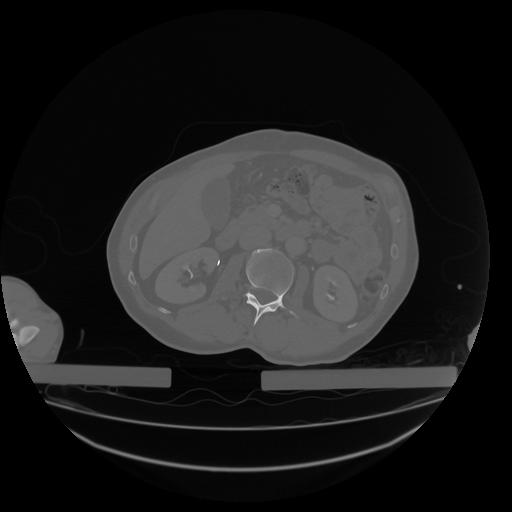

34 CUERPO,CE,Vol,1.0,CUERPO,,